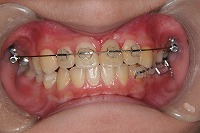

反対咬合と前歯が生えてこない事を主訴に来院された、10歳4か月の男の子です。診断「下顎骨の過成長による骨格性反対咬合で上顎正中の左方偏位と埋伏歯を伴う」1期治療で反対咬合の解消と埋まっていた前歯を牽引しました。